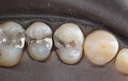

Mark Chun #13,14,15 pre-op

Mark Chun #13,14,15 amalgam removal